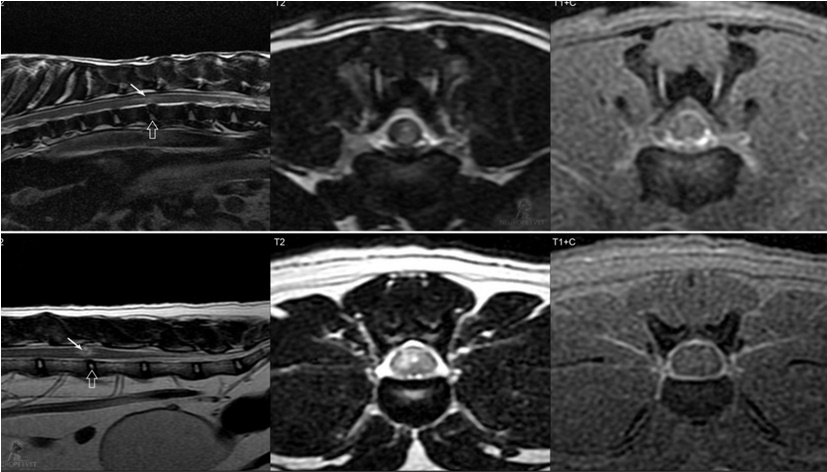

Το κλασσικό απεικονιστικό εύρημα είναι η παρουσία εστιακού σήματος αυξημένης έντασης από τη μια πλευρά του ΝΜ στην Τ2 ακολουθία πάνω από το υπεύθυνο μεσοσπονδύλιο διάστημα. Η αλλοίωση είναι, συνήθως, καλώς περιγεγραμμένη και συχνά προσβάλλει τη φαιά ουσία. Η αλλοίωση πιστεύεται ότι οφείλεται στο οίδημα του ΝΜ λόγω της θλαστικής κάκωσης.

Μερικές φορές διαπιστώνεται ήπια ενίσχυση του σκιαγραφικού στην ενδομυελική αλλοίωση ή στις μήνιγγες/επισκληρίδιο χώρο. Ο πηκτοειδής πυρήνας του προσβεβλημένου δίσκου έχει μικρότερο όγκο σε σύγκριση με τους πηκτοειδείς πυρήνες των γειτονικών μεσοσπονδυλίων δίσκων στην ακολουθία Τ2. Το μεσοσπονδύλιο διάστημα μπορεί να είναι ελαφρώς στενότερο από τα γειτονικά. Μερικές φορές, απεικονίζεται μικρός όγκος υλικού έξω από τη σκληρή μήνιγγα που μπορεί να είναι μικρή ποσότητα υλικού του δίσκου ή αιμορραγία από τα φλεβώδη σπονδυλικά πλέγματα που συνήθως ρήγνυνται κατά την εξώθηση του πηκτοειδή πυρήνα.

MRI από έναν σκύλο (επάνω σειρά) με ANNPE στο επίπεδο Θ12/13 και μια γάτα (κάτω σειρά) με ANNPE στο επίπεδο Ο4/5. Σημειώστε τη χαρακτηριστική ενδομυελική αλλοίωση με σήμα αυξημένης έντασης στις T2-ακολουθίες (γεμάτα βέλη), η οποία δεν παρουσιάζει ενίσχυση μετά την έγχυση σκιαγραφικού. Ο πηκτοειδής πυρήνας των προσβεβλημένων μεσοσπονδύλιων δίσκων (κενά βέλη) είναι μικρότερος σε σύγκριση με τους φυσιολογικούς γειτονικούς δίσκους. Παρατηρείται ήπια έως μέτρια μηνιγγική ενίσχυση.